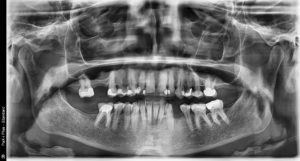

A 54-year-old female presents with a chief complaint that “I am interested in my options with my spaces from teeth being removed.”